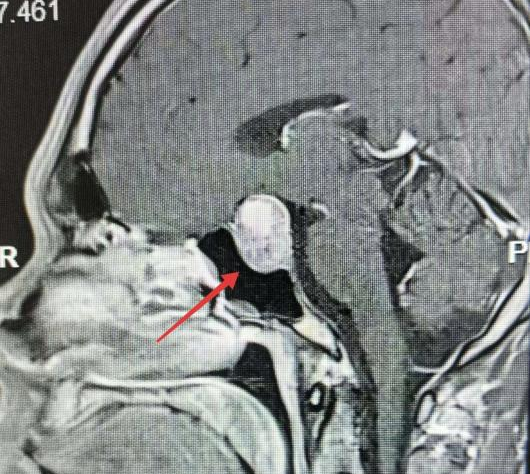

原以为是亚健康的他,在感觉到颈椎不适难以忍受后,来到南通市第一人民医院骨科就诊。可检测报告显示无明显异常。经过进一步检查,最终医生发现李先生大脑深处长出了一枚巨大的生长激素垂体腺瘤。

医生表示李先生已突发垂体瘤急性卒中,瘤体内出现出血坏死,随时可能引|发昏迷休克,几小时内就可能危及生命。

医生通过微创手术,切除了这枚肿瘤,术后李先生恢复良好。